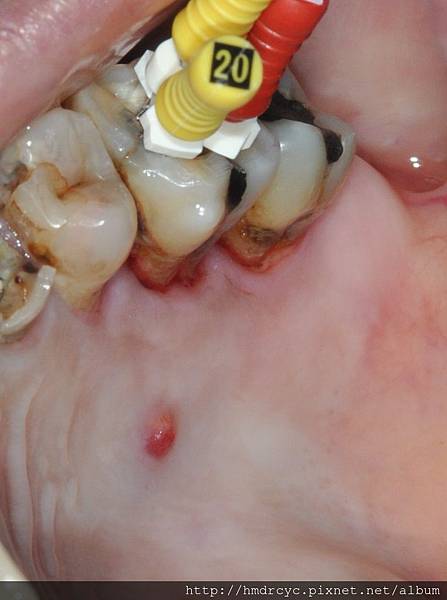

在口腔裡面的狀況就是這樣

嚴格的說膿包其實在骨頭裡面

在口腔裡面看到的是膿流出來的開口